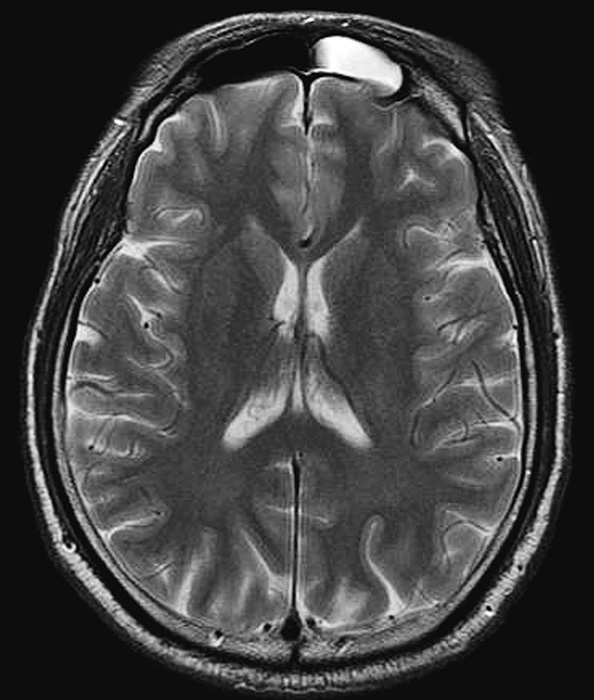

Typical Grade 3 case, a 59-year-old male who had 17 T2-elongated spots (White arrow) in the axial T2-weighted images.